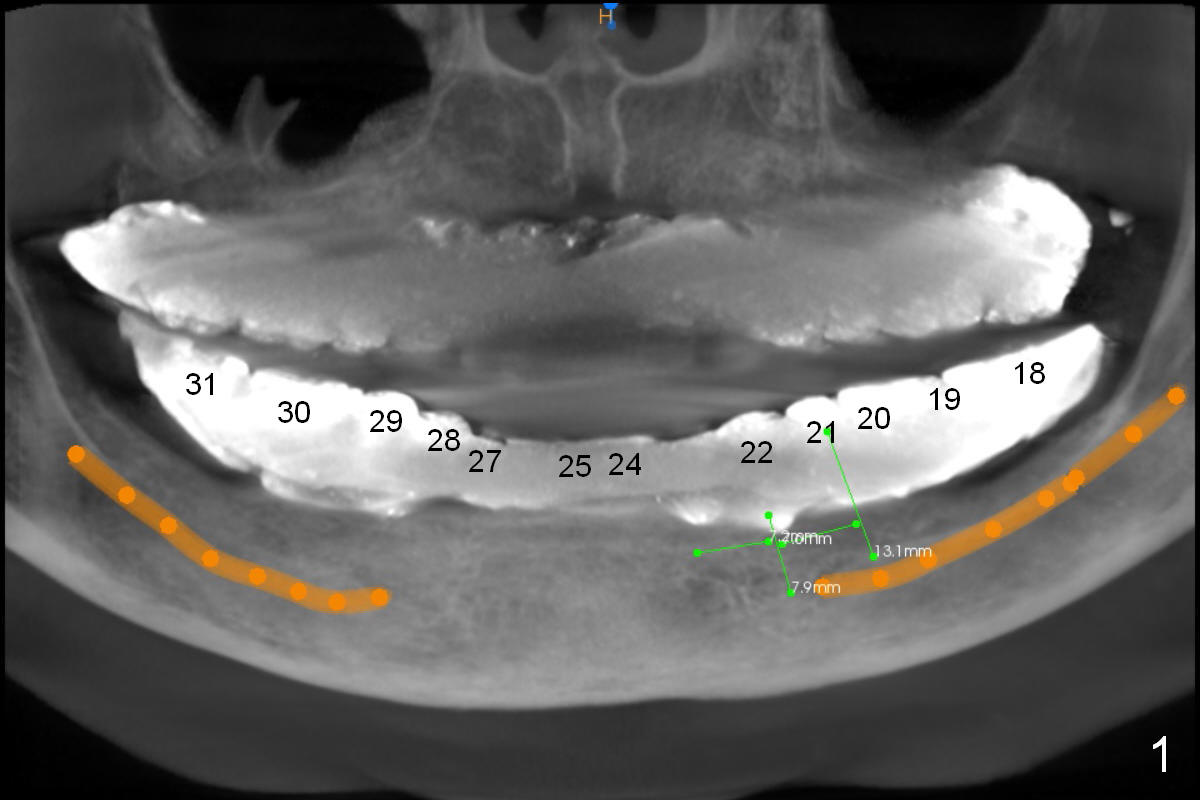

The patient wants to change unstable complete dentures to fixed ones.  Because the problem of pain is associated with the lower left (Fig.1 the left Inferior Alveolar Nerve is more superficial), the lower arch will be reconstructed first.  Totally 6 implants will be placed for bridges/crowns.  Due to time constraint, four implants are placed at the 1st stage (#21, 22, 27 and 28 (Fig.4,5,8,9)); the lower denture will be retained immediately by ball abutments and soft relined.  Two to three months later, two more implants will be placed (at #31 and 20, Fig.2,10).  Note severe atrophy of the crest at #18 and 19 (Fig.11 and 12).  If primary stability is achieved, a fixed immediate provisional will be fabricated.

In contrast to the upper arch, the bone density in the lower arch is high.  The challenge is bone height.  Short implants will be used (6 mm for #31 (Fig.2) and 8 mm for the majority of the others (at premolar and canine sites).  If needed, extra implants will be placed at incisor sites (Fig.6,7 (implant can be longer)) and at #29 (Fig.3) .  If a site is too small for a 3.8 mm 2-piece implant, a 1-piece one may be placed.